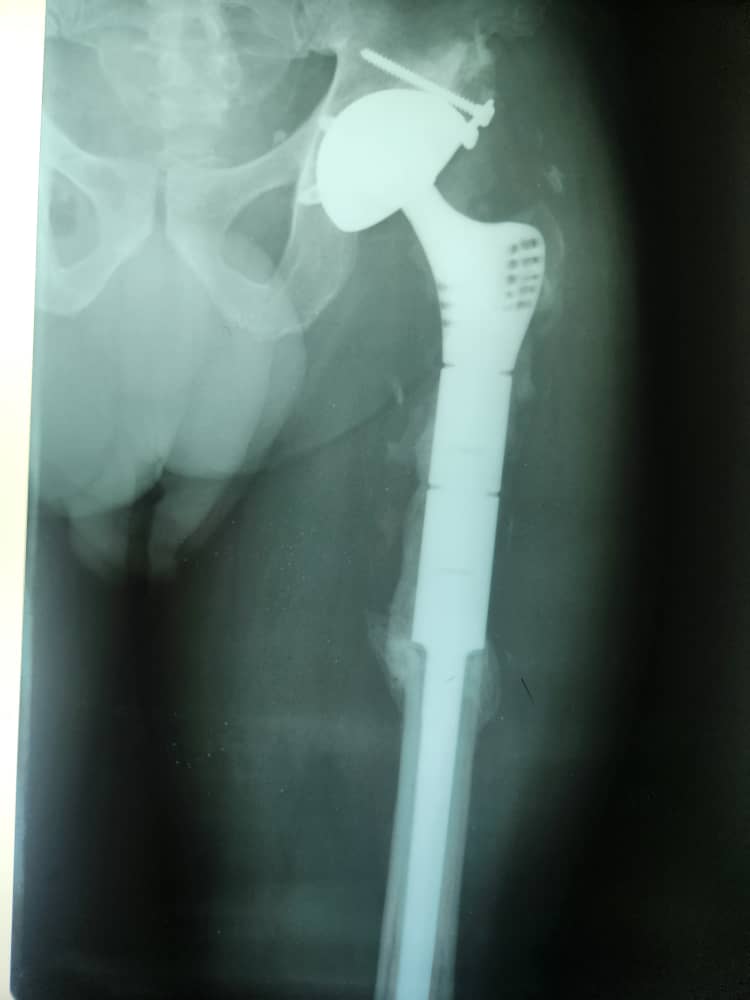

Galerie d’implants & imagerie

Exemples pédagogiques de prothèses et d’ostéosynthèses pratiquées à la CCL.

PTH — face